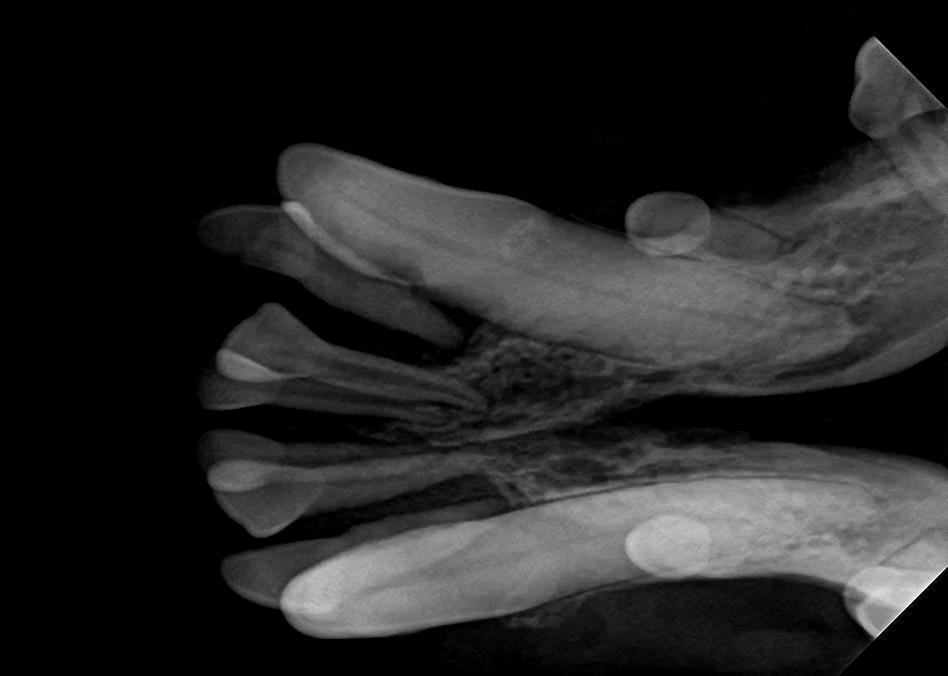

Examples of dental problems:

At A Couple of Vets, our animal hospital staff is well-versed in the latest dental cleaning techniques to remove plaque and tarter from the teeth’s surface as well as from below the gum line. We perform dental x-rays at every cleaning to ensure that the teeth are completely healthy. They may look good on the surface, but many problems occur below the gum line and are only visible with x-rays.